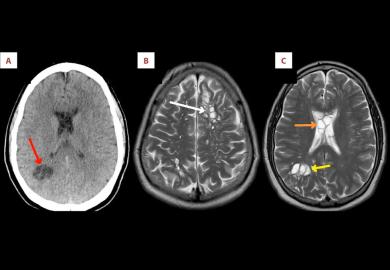

بهداشت و درمان شستوشوی بینی با آب شیر ممکن است به عفونت آمیبی مغزخوار منجر شود پزشکان میگویند اگر برای شستوشوی بینی از آب شیر استفاده میکنید، آن را دستکم یک دقیقه بجوشانید و بگذارید خنک شود آمیب مغزخوار چیست و چرا موجب مرگ میشود؟ مرگ پسربچه هفت ساله بر اثر ابتلا به آمیب مغزخوار کشف یک «آمیب» نادر مغزخوار در فلوریدا